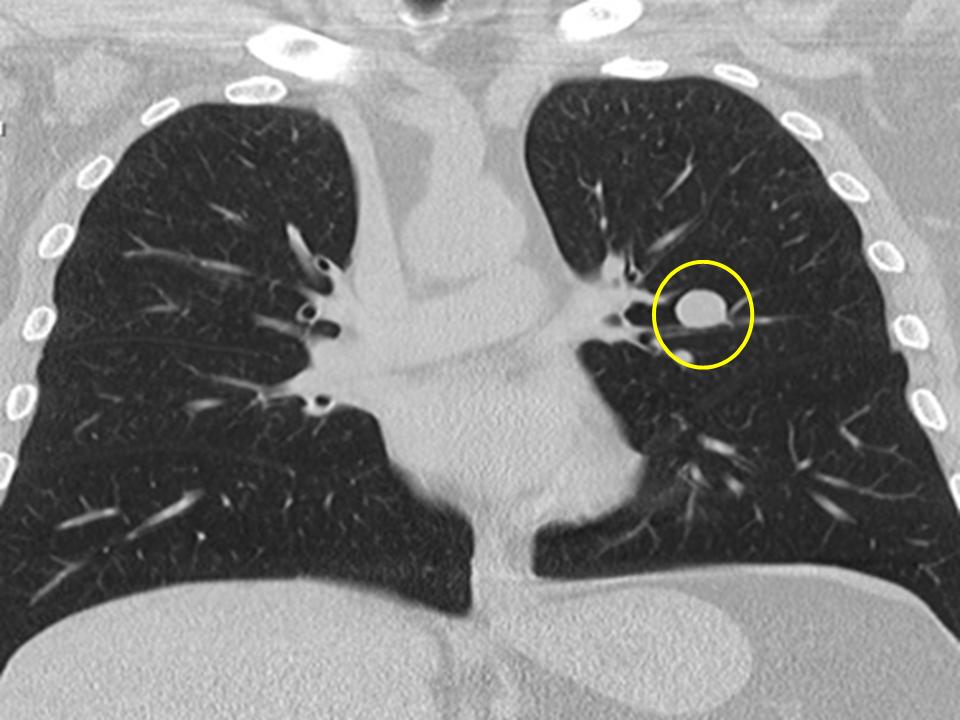

Гамартома удаление

Гамартома удаление 112 фото